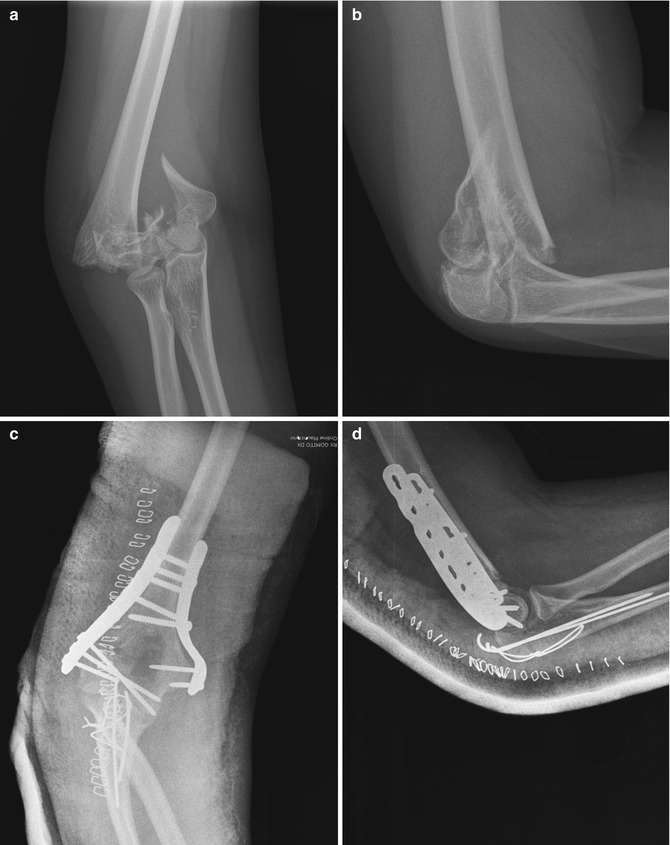

- The doctor may order basic x-rays. Depending on your unique health history and your treatment needs, the doctor may order additional laboratory tests or specialized x-rays.

- Basic elbow x-rays are taken from the front and side. Additional x-rays, taken at 2 different angles, also are routine.

Surgery

Sometimes an operation to repair your broken elbow is the best choice. This is particularly true if you have an open, or compound (a fracture in multiple pieces), elbow injury.

Elbow injuries that damage nerves and blood vessels often need to be fixed in the operating room. Medical researchers have found that certain types of broken elbows heal better if they are repaired in the operating room.

- Hardware problems: Doctors sometimes repair broken elbows with wires, pins, screws, plates, and other pieces of hardware.

During your elbow repair surgery, Dr. Dupay puts your bones back in place, sometimes securing them with metal pins or screws. This helps hold your bones together while they heal.